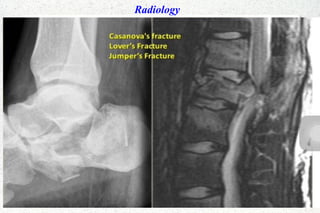

Radiology